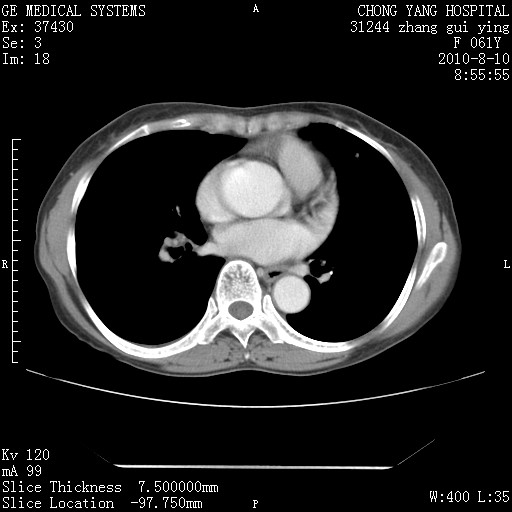

标题: CT28314:F61Y胸部增强,发热咳嗽一周入院,后面的为一周前平 [打印本页]

标题: CT28314:F61Y胸部增强,发热咳嗽一周入院,后面的为一周前平

1、支持考虑右侧中央型肺癌伴右肺中叶节段性不张及下叶支气管黏液痰栓    2、左肺上叶舌段感染。

支持3楼意见,还要考虑:纵隔及肺门淋巴结转移、右侧少量胸腔积液。

确切的说:1:右肺下叶中心型肺癌侵及中叶支气管并中叶不张,纵膈淋巴结转移。2:左肺舌叶炎症。3:右侧胸腔少量积液

块影平扫32hu,动静脉期62-70hu.

1:右肺下叶中心型肺癌侵及中叶支气管并中叶不张,纵膈淋巴结转移。2:左肺舌叶炎症。3:右侧胸腔少量积液。支持!

考虑右下肺肺癌,纵隔淋巴结转移i。

右肺下叶中心型肺癌侵及中叶支气管并中叶不张,纵膈淋巴结转移。2:左肺舌叶炎症。3:右侧胸腔少量积液